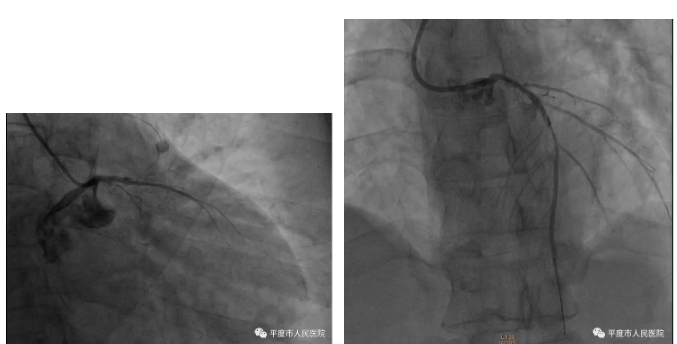

近日滕大叔又因左右再发胸痛,胸骨后闷痛,伴恶心、呕吐,呕吐物为胃内容物,伴出汗,持续不缓解,遂至我院急诊,我院心内科张少君主治医师接诊患者后反复复查3次心电图均为大致正常,但通过详细查体及询问病史及体格检查,初步考虑患者为“心源性高危胸痛”可能,建议患者急诊行冠脉造影,征患者及家属同意后入导管室直接开始手术,冠脉造影见左主干正常;左前降支、回旋支近端闭塞,右冠状动脉后三叉可见85%狭窄,此时患者随着病情的加重血压进行性下降,最低可至80/40mmHg。

面对这样的造影结果,我们同时为患者捏了一把汗,两根大血管闭塞,仅剩的第三根血管还有重度狭窄,患者生命命悬一线,死亡率90%以上,患者目前生命体征不稳定,继续介入手术也是极高风险。手术医师当机立断,给予患者IABP支持下行介入治疗,功夫不负有心人,在大家的共同努力下,患者顺利的完成了手术,前降支血流完美恢复,患者顺利的闯过了一关,但作为医生我们丝毫不敢放松警惕,我们明白等待我们的是再灌注心律失常关口、休克关口、心衰关口,丝毫的放松都可能前功尽弃。幸亏患者有IABP的支持,术后患者入住我科CCU,专职护士每天密切监测生命体征,最终在大家的共同努力下,过五关、斩六将,术后第5天患者各项指标平稳,顺利拔除IABP。